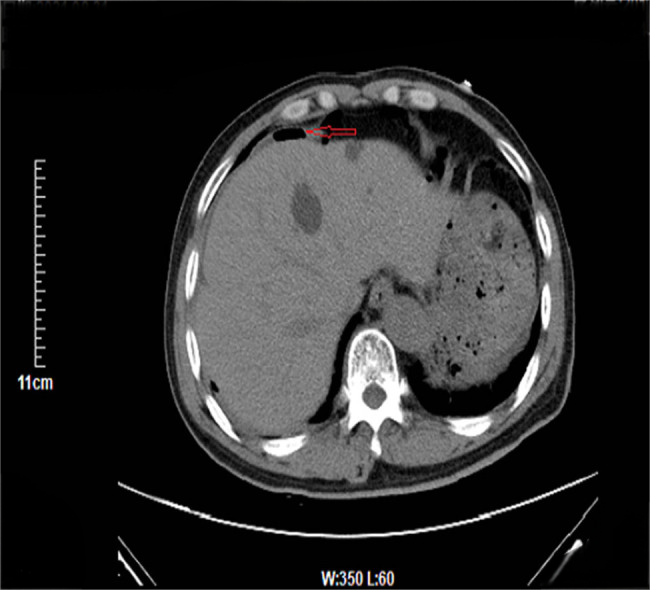

病史摘要:30岁男性患者,有大量饮酒史,无吸烟及非法药物使用史,否认胃肠道恶性肿瘤等家族史。因精神状态改变被送至急诊科。 诊疗过程:初始检查发现中度转氨酶升高,尿毒物筛查大麻素阳性,多种病毒血清学阴性。影像学检查发现孤立性左肾、输尿管结石伴急性肾损伤及腹腔肿块等。肿瘤标志物大多正常,LDH升高等。CT引导下活检,病理及免疫组化有相应表现。初步诊断为起源于胰腺的异位肝细胞癌伴广泛转移,先接受